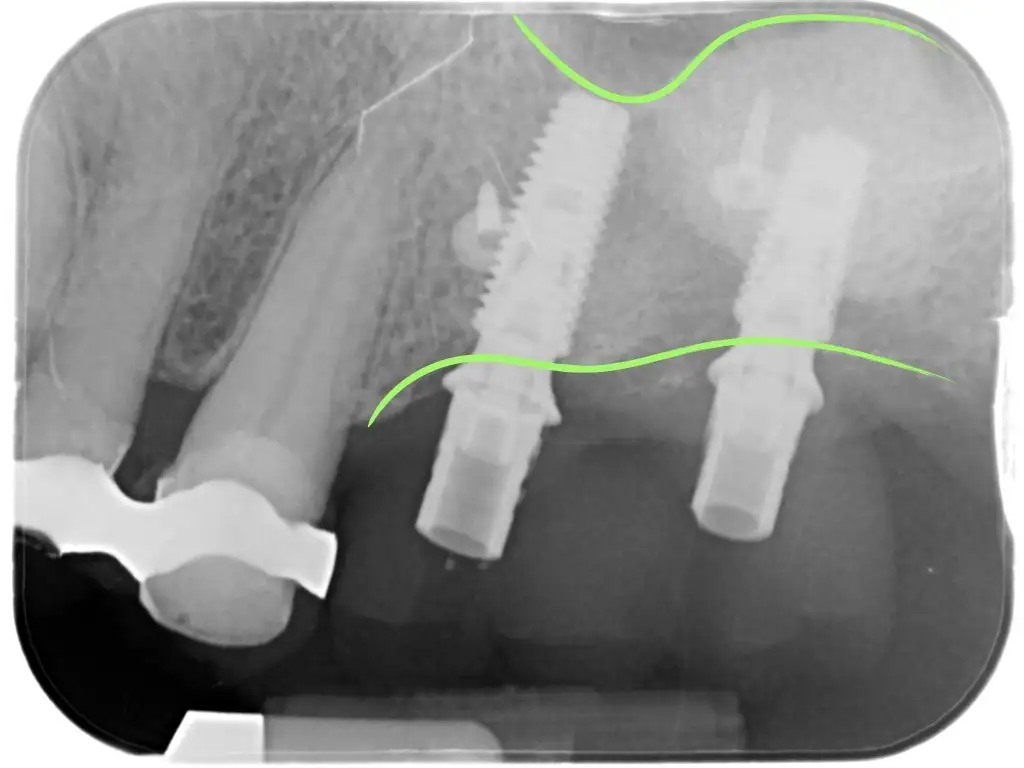

Questo sicuramente è un approccio estremamente valido per riabilitare un’arcata intera. Molto spesso il riassorbimento osseo è importante ma possiamo ancora individuare delle aree in cui posizionare alcuni impianti in maniera strategica.

E’ stato dimostrato che con le opportune tecniche (come ad esempio l’All-on-four) anche solo 4 impianti sono in grado di sostenere un’arcata dentale intera. In più in questi casi i denti possono essere inseriti entro 48 o anche 24 ore dall’intervento evitando di dover restare senza denti o portare protesi mobili provvisorie.

L’intervento viene inoltre eseguito in sedazione: la persona è cosciente ma non sente nulla, non si accorge di nulla e al “risveglio” ricorda solo una sensazione di serenità e leggerezza.

Nel giro appunto di 24-48 ore potrà tornare a sorridere e mangiare grazie alla protesi fissa a carico immediato.